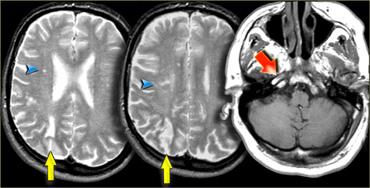

Bên trái là hình ảnh của bệnh nhân có các ổ nhồi máu nhỏ ở bán cầu phải tại vùng ranh giới sâu (đầu mũi tên màu xanh lam) và tại vùng ranh giới vỏ não giữa lãnh thổ ĐM não giữa (MCA) và ĐM não sau (PCA) (mũi tên màu vàng).

Có bất thường tín hiệu tại động mạch cảnh phải (mũi tên màu đỏ) do hậu quả của tắc mạch.

Bên trái là một ví dụ khác về các ổ nhồi máu nhỏ tại vùng ranh giới sâu và vùng ranh giới vỏ não giữa lãnh thổ ĐM não giữa (MCA) và ĐM não sau (PCA) ở bán cầu trái.

Bên trái là ví dụ về nhồi máu tại vùng ranh giới sâu và vùng ranh giới vỏ não giữa lãnh thổ ĐM não trước (ACA) và ĐM não giữa (MCA).

Bất thường cường độ tín hiệu tại động mạch cảnh phải là hậu quả của tắc mạch.

Sự kết hợp các dấu hiệu này rất phổ biến đến mức một khi đã nhận biết được hình thái, bạn sẽ gặp lại nhiều lần.